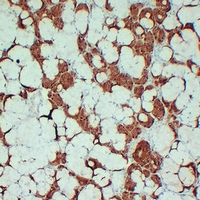

Immunohistochemical analysis of S100-A1 staining in human salivary gland formalin fixed paraffin embedded tissue section. The section was pre-treated using heat mediated antigen retrieval with sodium citrate buffer (pH 6.0). The section was then incubated with the antibody at room temperature and detected using an HRP conjugated compact polymer system. DAB was used as the chromogen. The section was then counterstained with haematoxylin and mounted with DPX.